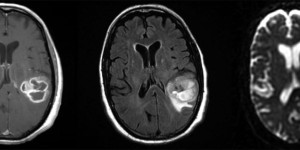

- Imaging: Partially calcified T2 heterogeneous, hyperintense subcortical/cortical mass with patchy or minimal contrast enhancement. Most often found cortically in the frontal or temporal lobes.

Attributed by RadsWiki, CC BY-SA 3.0, via Wikimedia Commons, https://upload.wikimedia.org/wikipedia/commons/2/28/Oligodendroglioma_001.jpg, https://upload.wikimedia.org/wikipedia/commons/9/9b/Oligodendroglioma_007.jpg

- Pathology: Cells with a “fried egg” appearance with monotonous round nuclei, surrounded by prominent perinuclear halos.

- Treatment: Surgical resection followed by radiation and chemotherapy.